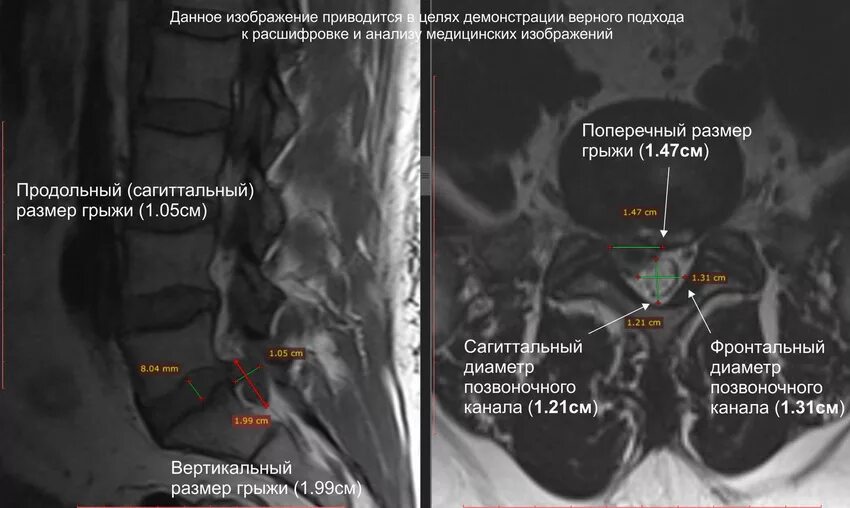

Какой размер грыжи считается большим